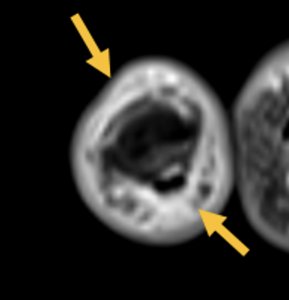

- Ausgeprägte Tenosynovitiden, v.a. der Flexorensehnen (Pfeile) (T1 FS KM)

- Diffuses Weichteilödem entlang des 5. Strahles mit korrespondierender KM- Aufnahme (Pfeile) (T1 FS KM)

- Diffuses Weichteilentzündung eines ganzen Strahls – hier ist hauptsächlich der 5. Strahl betroffen, vereinbar mit einer klassischen Daktylitis

- Diffuse ausgeprägte Tenosynvitiden